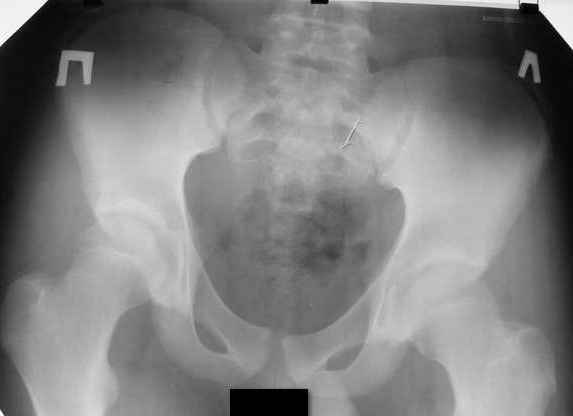

Больной Н., мужчина 18 лет с укорочением бедра и рекурвацией коленного сустава. Из анамнеза: огнестрельное сквозное пулевое ранение бедра 9 лет назад в н/3 левого бедра. Раны зажили без гнойных осложнений. Жалобы на укорочение левой нижней конечности и нестабильность в коленном суставе. При обследовании выявляется рекурвация коленного сустава. Абсолютное укорочение порядка 5см, стоя 8 см (за счет рекурвации). Имеется умеренный компенсаторный сколиоз. С передне-наружной стороны располагается рубец от входного отверстия, с задне-медиальной стороны от выходного. Можно предположить повреждение при травме зоны роста бедренной кости и задне-внутренних стабилизирующих структур коленного сустава. Предлагается обсудить тактику лечения: начать с удлинения бедра или со стабилизации коленного сустава, а также - на каком уровне производить удлинение бедра.A male 18 years old with shortened femur.Trauma 9 ears ago: gunshot wound with bullet of the left knee. It Is Reeked have healed without festering complications. The patient have shorter femur and recurvatum instability of knee joint. Absolute shortening is 5 cm, at standing up 8 cm (genu recurvatum). The input scar is situated on the antero-lateral side and output scar is on the postero-medial side. It is possible to expect damage by trauma of the growing zone of the femur and back-internal stabilizing structures of the knee joint. We discuss the treatment options: to begin with lengthening of the femur or preferably with stabilizations of the knee joint. What is the optimal level to produce the lengthening of the femur in this case.